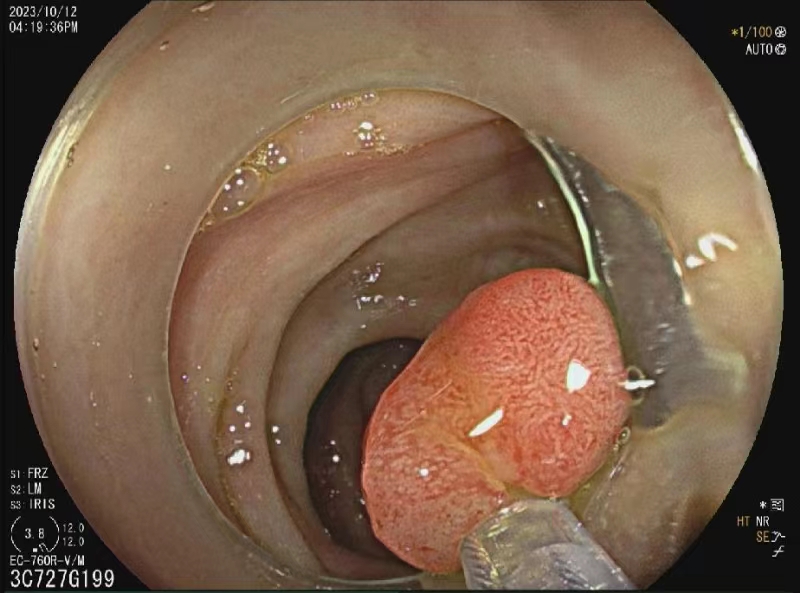

为方便广大人民群众咨询就诊,彝良县人民医院消化内科增设消化内科胃肠镜门诊。胃肠镜门诊于2023年12月顺利开诊。消化内科胃肠镜门诊将会帮助患者方便、快捷、及时完成胃肠镜检查、完成早癌筛查,远离胃肠道疾病。同时提供胃肠镜咨询、预约、检查、检查结果判读、评估手术风险及可行性,解读胃肠镜标本病理报告,为胃肠道疾病患者提供综合性治疗方案。为术后患者制定随访计划并追踪随访。对不明白胃肠镜检查注意事项的患者,特别是不明白肠镜检查前准备事项及肠道清洁药物服用方法的患者提供指导。 诊疗范围 1. 胃肠镜检查咨询、预约、检查; 2. 胃肠镜检查结果及病理结果分析、判读; 3. 胃肠镜下治疗评估及制定治疗方案; 4. 胃肠镜下早癌筛查,消化道出血、息肉、肿瘤的诊断及治疗; 5. 胃肠镜治疗后随访; 6. 幽门螺旋杆菌感染诊断及治疗。 坐诊时间 周三:上午08:00-11:30 ,下午14:30-17:30 周五:上午08:00-11:30 ,下午14:30-17:30 EMR术 结肠 欢迎关注“彝良县人民医院微信公众号”,方便您就医(提供预约挂号、缴费、检验检查报告查询、住院清单查询等服务)。 供稿:田应香、代堂伟 编辑:李 菲 审核:龙 海